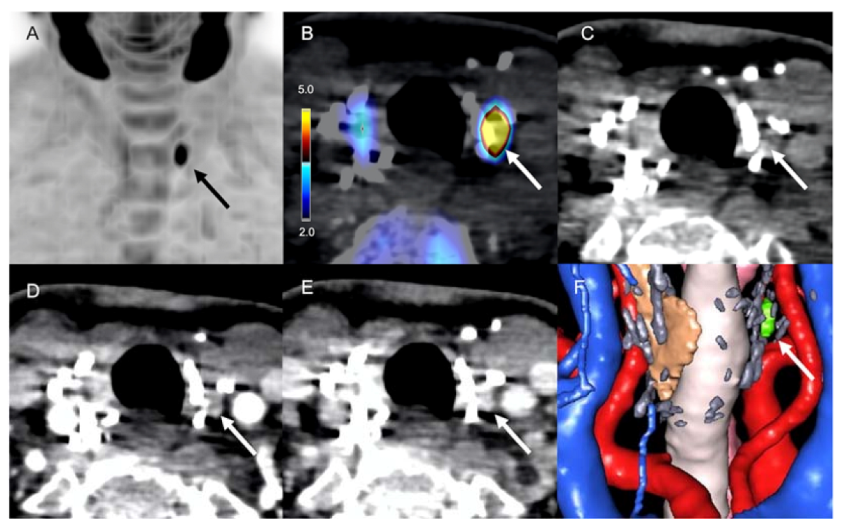

- Pretet, V.; Rotania, M.; Helali, M.; Ignat, M.; Vix, M.; Imperiale, A. 18F-Fluorocholine PET and Multiphase CT Integrated in Dual Modality PET/4D-CT for Preoperative Evaluation of Primary Hyperparathyroidism. J. Clin. Med. 2020, 9, 2005. [Google Scholar] [CrossRef] [PubMed]